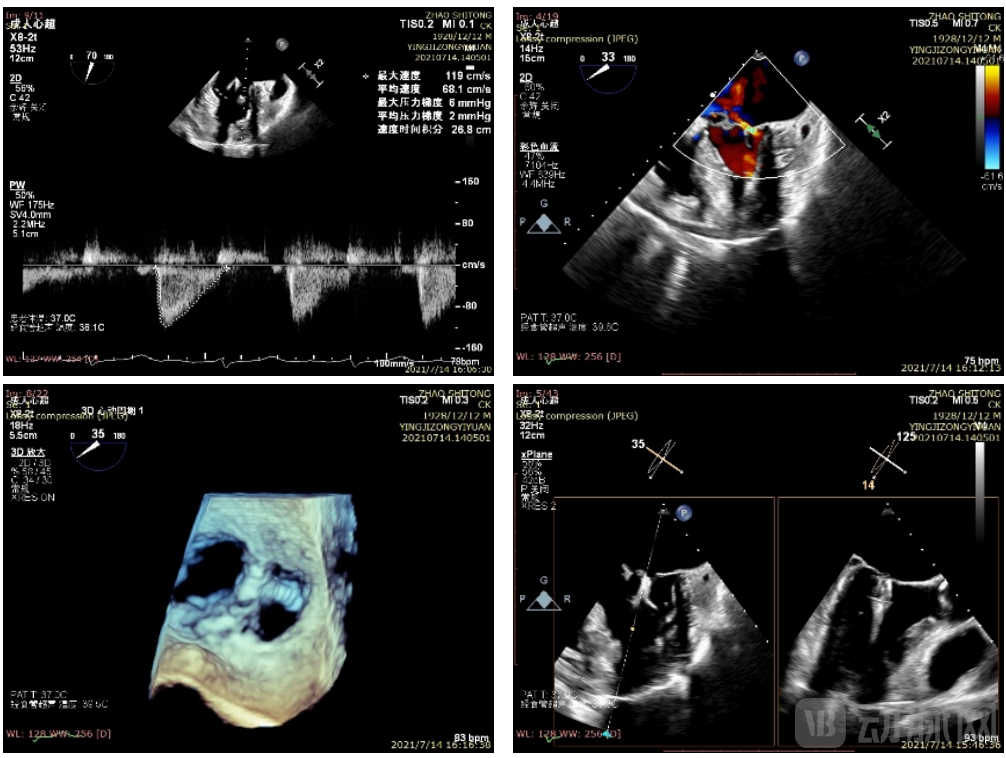

手术于2021年7年14日14:20在心外科手术室进行,术后患者各项指标平稳,夹合部位良好,二尖瓣轻度反流,手术在2小时内顺利完成。

患者术后超声图(TEE)